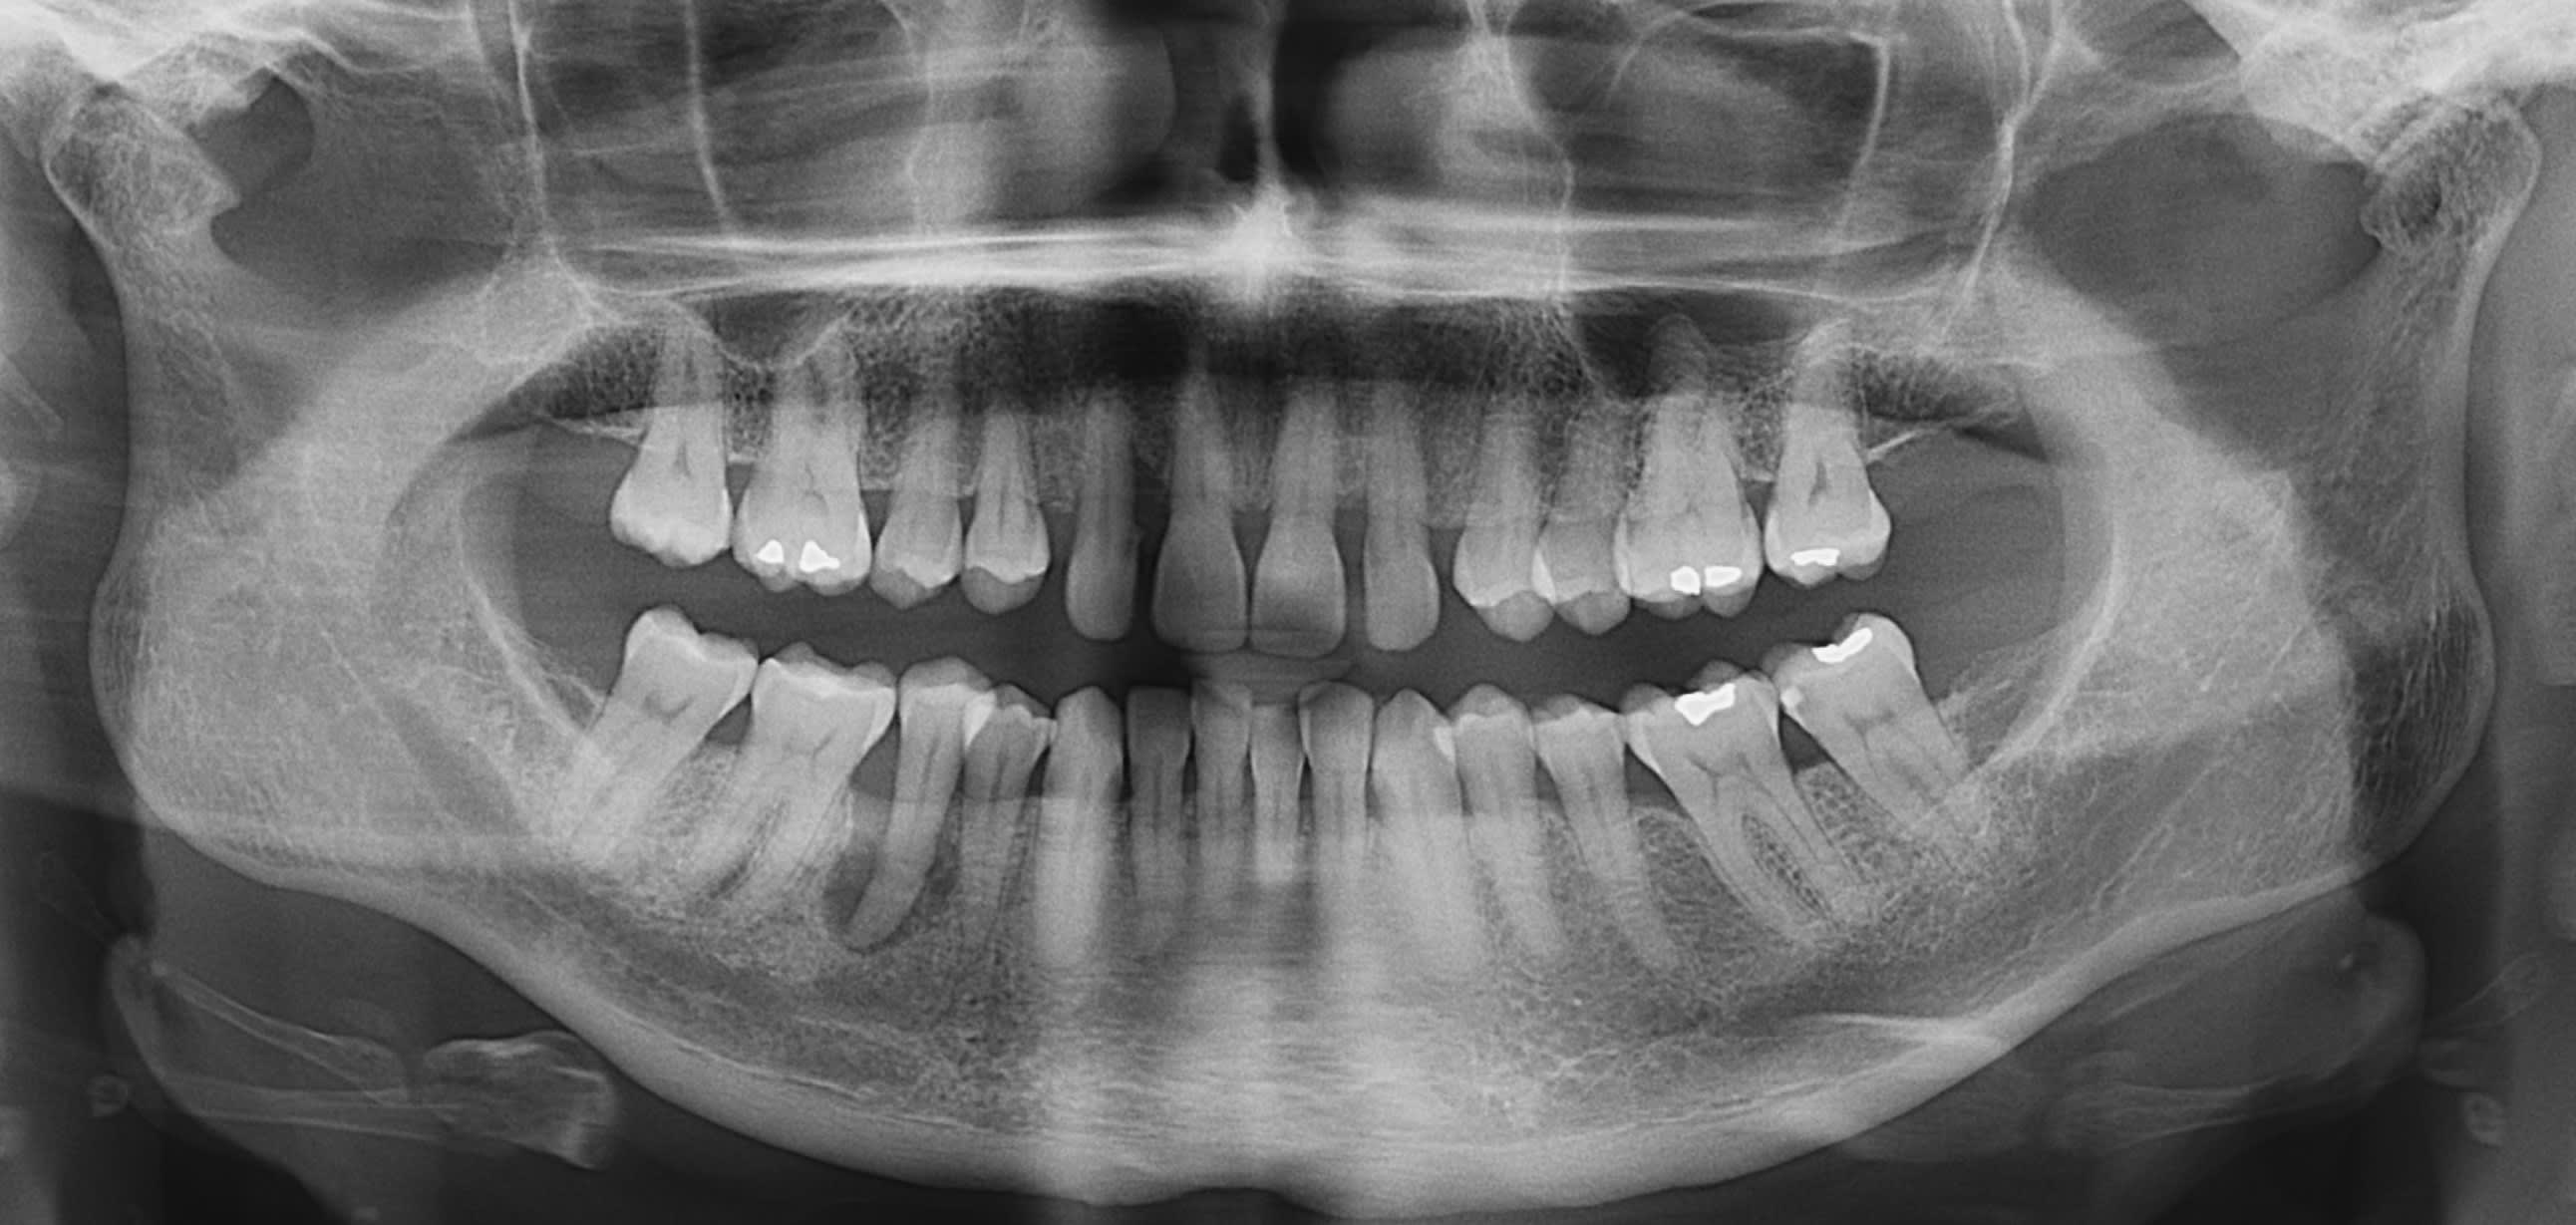

Voilà un cas que je n'arrive pas à m'expliquer.

Patiente 50 ans , non fumeuse, hygiène nickel et qui arrive avec une 45 qui va être perdue.

Avez-vous une idée de la cause de ce genre de chose ?

l occlusion...

la 12 ca va pas fort non plus...

C est surtout qu il lui manque les 3 du haut.

Alors elle se retrouve en sur contact antérieur qu e ulle compense en allant à droite .

Endo de la pm , equilibration et ça ira .

Pas de protection canine car pas de 13 et 23 .

la 31 n'est pas au mieux non plus

ce qui est probable c est que le ttt endo + equilibration occluale permettra de conserver la dent.

fais deja ca et tu reevalues dans 3 mois.

C'est moi ou elle n'est pas dans l'alignement des autres vu la superposition?

Elle est vitale?

Mes hypothèses sur la base d'une pano:

Fêlure verticale, clairement le plus probable.

Bourrage alimentaire chronique à cause d'un point de contact inadapté

Nécrose suite à un trauma, ayant évolué en endoparo (même si l'aspect m'évoque plus une origine paro que endo).

L'occlusion j'y crois peu/pas comme cause: pour causer des dégâts à ce point il aurait fallu une surcharge occlusale telle qu'il y aurait eu des douleurs type desmodontite depuis longtemps (ou alors elle est particulièrement insensible.

Possible facteur ayant aggravé la situation par contre.

Et comme hokusai: commence par un bon traitement endo et élimine une éventuelle surcharge occlusale, ça se tente.

Traitement paro éventuel en complément selon ce que donne le sondage.

Cette 45 est très vraisemblablement fracturée verticalement.

Après une petite perte osseuse peut mettre a nu un canal latéral et entraîner aussi une nécrose…